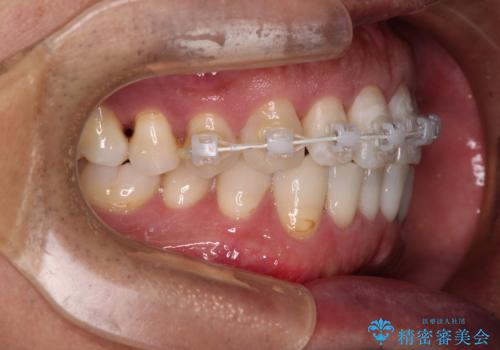

内側にある歯が干渉する 上顎前歯の部分矯正

- 上顎の前歯が内側にあり、下顎のセラミッククラウンと干渉することが気になるとのことで来院された患者様です。

上顎前歯にワイヤー装置を装着し、セラミッククラウンとは干渉しないようにしながら歯列を整えることとしました。

セラミッククラウンとの干渉はすぐに改善され、歯列も整いましたが、一方で、前歯で食事が噛みにくくなり、1年近い治療期間となりました。